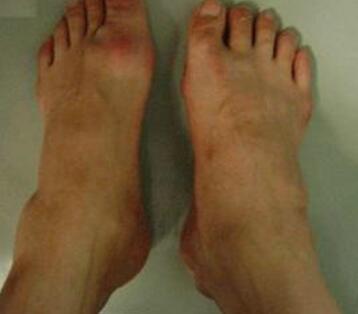

治疗一个疗程后,张先生感到明显的变化,手脚的肿胀处清楚的可以看出消肿了很多,疼痛感也有明显的减小,痛苦折磨减轻很多。...[详细]